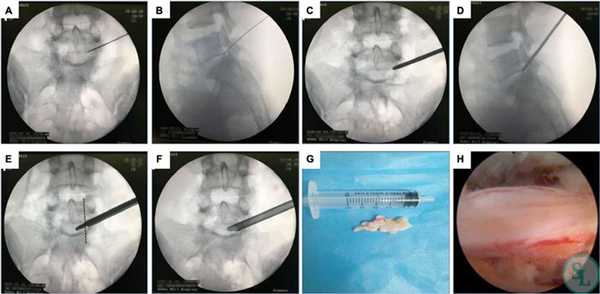

Составить представление о том, как эндоскопическим методом производится освобождение сдавленных составляющих элементов нервной и кровеносной системы в позвоночнике, вам поможет информация:

- Как правило, операция проходит под местной анестезией, но возможно и использование общего эндотрахеального наркоза.

- Далее следует обработка антисептическим раствором кожных покровов спины, если доступ создается сзади. На коже в проекции места поражения выполняется маленький разрез (не более 1,5 см) скальпелем.

- В созданное отверстие под контролем ЭОП в безопасную зону позвоночного пространства вводится дилататор (расширитель), затем по нему вводится рабочая гильза, и уже через гильзу устанавливают трубку эндоскопа. В основном приборе подключают камеру и световод.

- Под многократно увеличенным видеонаблюдением, используя сменные инструменты, которые помещаются внутрь эндоскопа, хирург выполняет необходимые манипуляции. Специалист аккуратно удаляет источник компрессионного синдрома, например, остеофиты костными кусачками, грыжу диска микрощупом. Таким образом, достигается декомпрессия нервов или сосудов, которые смогут восстановиться уже в скором времени.

- Иссеченные структуры выводятся через отсек эндоскопической системы, полость позвоночного канала тщательно промывается физиологическим раствором от хирургического «мусора». Далее прибор извлекается, после чего ранку дезинфицируют и накладывают на нее несколько швов.

Суть операции заключается в следующем:

- Кожные покровы обрабатываются раствором антисептика, и выполняется разрез в проекции позвонка, провоцирующего развитие неврологической симптоматики.

- Через разрез в безопасную зону позвоночного пространства вводится расширитель под контролем ЭОП. По нему погружается рабочая гильза, сквозь которую проводят трубку эндоскопа. Ее диаметр составляет 6-8 мм. Подключают светодиод и камеру, моментально начинающую трансляцию изображения на монитор.

- Под многократным увеличением с помощью специальных инструментов, вводимых в операционное поле через трубку эндоскопа и сменяемых в ходе операции, нейрохирург выполняет резекцию патологически измененных тканей. Он последовательно устраняет образование, ставшее причиной развития компрессионно-вертебрального синдрома. Так для резекции костных остеофитов используются специальные кусачки, а для удаления грыжи межпозвоночного диска - микрощуп.

- Удаленные фрагменты выводятся из организма посредством специального отсека эндоскопической системы, а образовавшаяся полость тщательно промывается физиологическим раствором.

- Оборудование извлекают, а на послеоперационную рану накладывают швы.